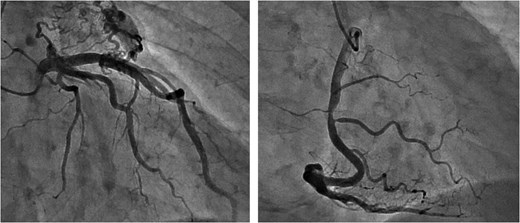

A 73-year-old male presented to his primary hospital with complaints of chest pain. Examination revealed a coronary artery-pulmonary artery fistula and 75% stenosis of the RCA (Figs 1 and 2) with a resting full-cycle ratio (RFR) of 1.0. However, myocardial scintigraphy was negative for ischemia and electrocardiogram (CAG) at rest showed no ST changes (Fig. 3). An exercise resting electrocardiogram (ECG) showed diffuse ST depression, raising suspicion of ischemia due to coronary steal (Fig. 4). Consequently, the patient was referred to our department.

Preoperative CAG showing coronary artery-pulmonary artery fistula and 75% stenosis of the right coronary artery.